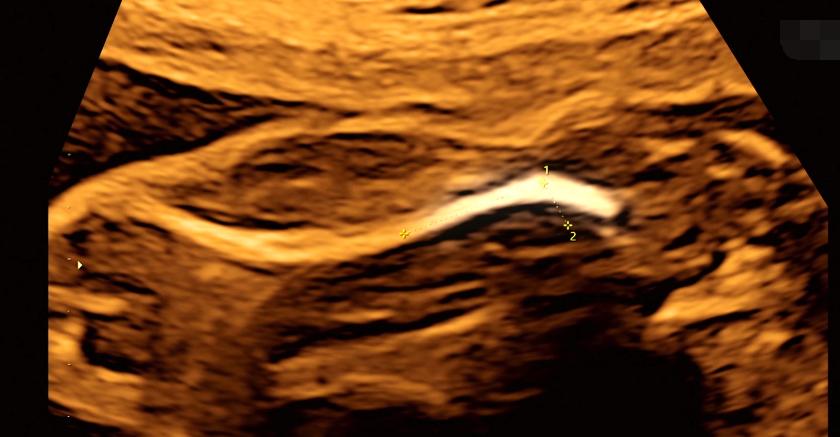

巴斯基医生决定采用间质内激光治疗,也就是把一根非常细的针从贝基的腹部穿刺进入胎儿的肺里,再把激光纤维插进细针中,通过发射高能的激光脉冲来堵住那根输送血液和营养物质的供血管

贝基的手术日很快到来,巴斯基医生评估这次手术的风险系数极高,手术是在胎儿的3.5-4厘米大的胸腔内进行,供血管的粗细不到一根火柴棍,而肿瘤却有拇指那么大,一旦手术进行中出现1、2毫米的误差,后果将不堪设想。

巴斯基医生耐心地告知贝基手术流程,首先他需要穿过贝基的腹部给胎儿先打一针麻醉剂,这样才可以确保孩子不会在肚子里乱动,贝基强忍着针头从肚子上扎进去的刺痛,但她没有任何怨言,为了自己孩子的健康和平安,母爱的力量变得无比伟大。

等待麻药生效后,巴斯基医生需要重新把一根更粗的针扎进胎儿的囊肿位置,因为贝基作为怀孕的母亲没有办法打麻醉,当医生用力把针管扎进去时,贝基疼的整个人都颤抖了起来。

巴斯基医生只能依靠模糊的B超投影仪来寻找肿瘤的位置,尽管如此,他还是凭借丰富的经验将针管快狠准地扎进了准确位置,接着激光纤维的导入也很顺利,巴斯基医生没有丝毫犹豫,迅速找到了供血管的位置并利用激光堵住了它,不一会B超显示胎儿正在向胎盘泵血了,这就意味着手术结果的顺利和成功,巴斯基医生的沉稳操作甚至让肚子里的胎儿没有察觉到任何异常,听到这个天大的好消息,贝基和丈夫都喜极而泣,现在,她的女儿终于可以平安长大了。